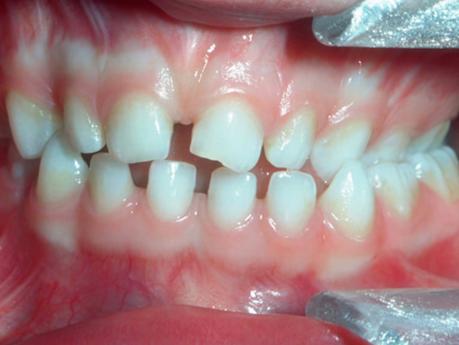

非营养性吮吸习惯可能与乳牙列和混合牙列的错牙合畸形患病率增加以及上前恒牙外伤的发生风险增加相关。可能会出现以下图片中的问题,包括前牙开牙合;后牙反牙合;深覆盖和上颌相对下颌过于前突的Ⅱ类错牙合。